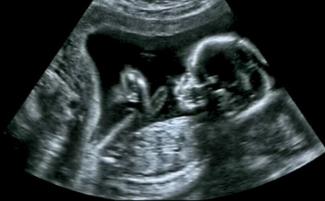

Jen a John Adkinsovci pre CNN uviedli, že chcú veľkú rodinu a tešili sa, že svojmu dvojročnému synovi dajú súrodenca, keď sa dozvedeli, že Jen je tehotná. CNN uvádza, že manželia boli “nadmieru” šťastní z tehotenstva, ale v 12. týždni sa ich “plány rozbili počas rutinného ultrazvukového vyšetrenia.”

“Hneď ako mi ultrazvukový technik priložil tú paličku na brucho a ja som na obrazovke uvidela dieťa, vedela som, že niečo nie je v poriadku,” povedala Jen. “Jednoducho som povedala, ‘že’je tam veľa tekutiny, ktorá’tam nemá byť.’”